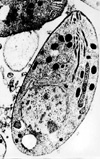

above: T. gondii: T.gondii encephalitis (TE) is the most common cerebral opportunistic infection in patients with AIDS. The typical lesion is an ipodense focal area with ring contrast-enhancement and edema.(CT scan of a toxoplasmic encephalitis).